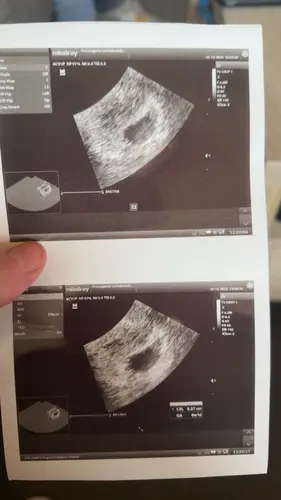

Afgelopen maandag ongeveer 8 weken ❤️ van kruin tot stuit 1,6cm